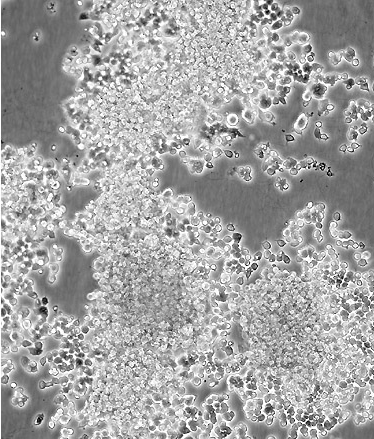

PC-12(高分化)

中文名稱 大鼠腎上腺嗜鉻細胞瘤細胞(高分化)

組織來源 腎上腺嗜鉻細胞瘤

細胞種屬 rattus norvegicus, rat

生長特性 adherent

培養基 RPMI-1640+10% FBS+1% P/S

形態特征 polygonal

細胞描述 該細胞系來自能移植的雄性大鼠腎上腺嗜鉻細胞瘤。這些細胞表達神經生長因子(NGF)受體。NGF可誘導產生神經表型。這些細胞不合成腎上腺素。